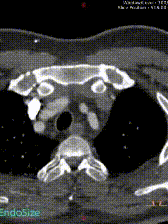

患者既往有高血压病史且控制不佳,体型肥胖。入院查体显示右下肢疼痛、麻木、冰凉、紫绀,肌力已降至0级,CK显著升高。当地医院紧急行CTA检查,虽然图像质量欠佳,但仍能清晰辨识:B型主动脉夹层,破口位于左锁骨下动脉根部,直径约25mm,真腔在膈肌水平几乎完全闭塞,同时存在明显的下肢及内脏缺血表现,伴有腹胀等内脏缺血症状。

三维重建评估:清晰显示夹层破口位置、大小及真腔受压情况